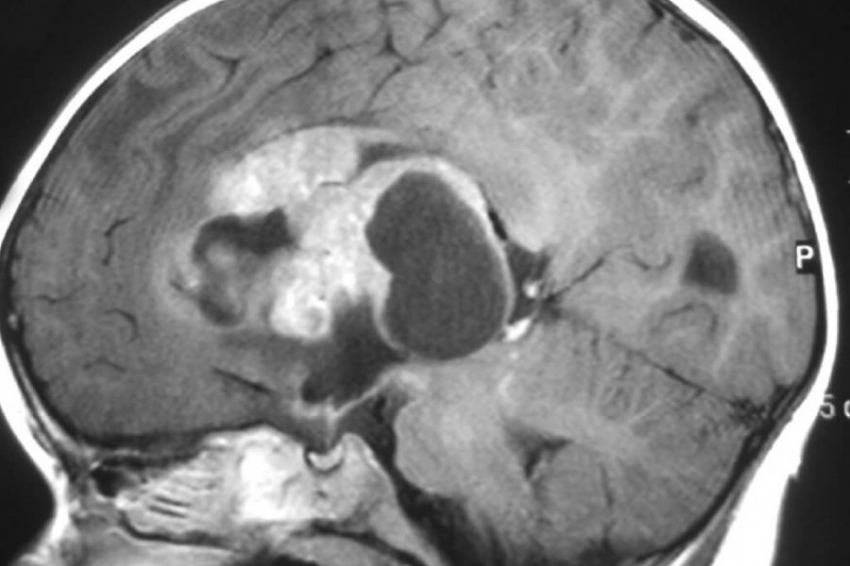

Магнитно-резонансная томография представляет собой современный метод диагностики, широко применяемый в медицине. Важно отметить, что данный метод не связан с использованием рентгеновского либо ионизирующего излучения, которое требует осторожности в частом применении.

Существуют определенные противопоказания для проведения МРТ, такие как первый, третий триместры беременности, наличие кардиостимуляторов, инсулиновых помп, имплантатов, металлических предметов, которые могут быть намагничены, и состояние клаустрофобии.